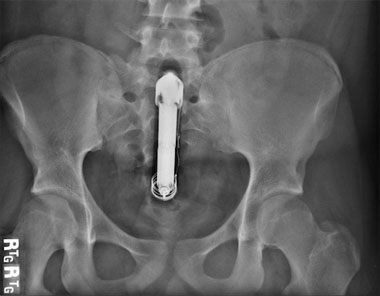

Met het schaamrood op haar kaken bekent de vrouw dat ze een vibrator in haar vagina heeft ingebracht, die ze er niet meer uitkrijgt. Ook de broeders op de Eerste Hulp lukt het niet de vibrator, die overdwars klemzit, te verwijderen. Een operatie is noodzakelijk.